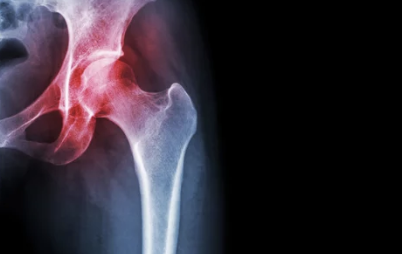

고관절은 골반과 허벅지 뼈가 연결된 부분으로, 엉덩이와 사타구니 부근, 허벅지 앞뒤, 옆쪽까지 통증이 나타날 수 있습니다.

1️⃣ 퇴행성 고관절염

- 설명: 고관절 연골이 닳아 없어지면서 염증과 통증 발생

- 주로 나타나는 연령: 50세 이상 중장년층

- 주요 증상:

- 사타구니 쪽 통증, 뻣뻣함

- 걷거나 오래 서 있을 때 통증 악화

- 관절 운동 범위 감소